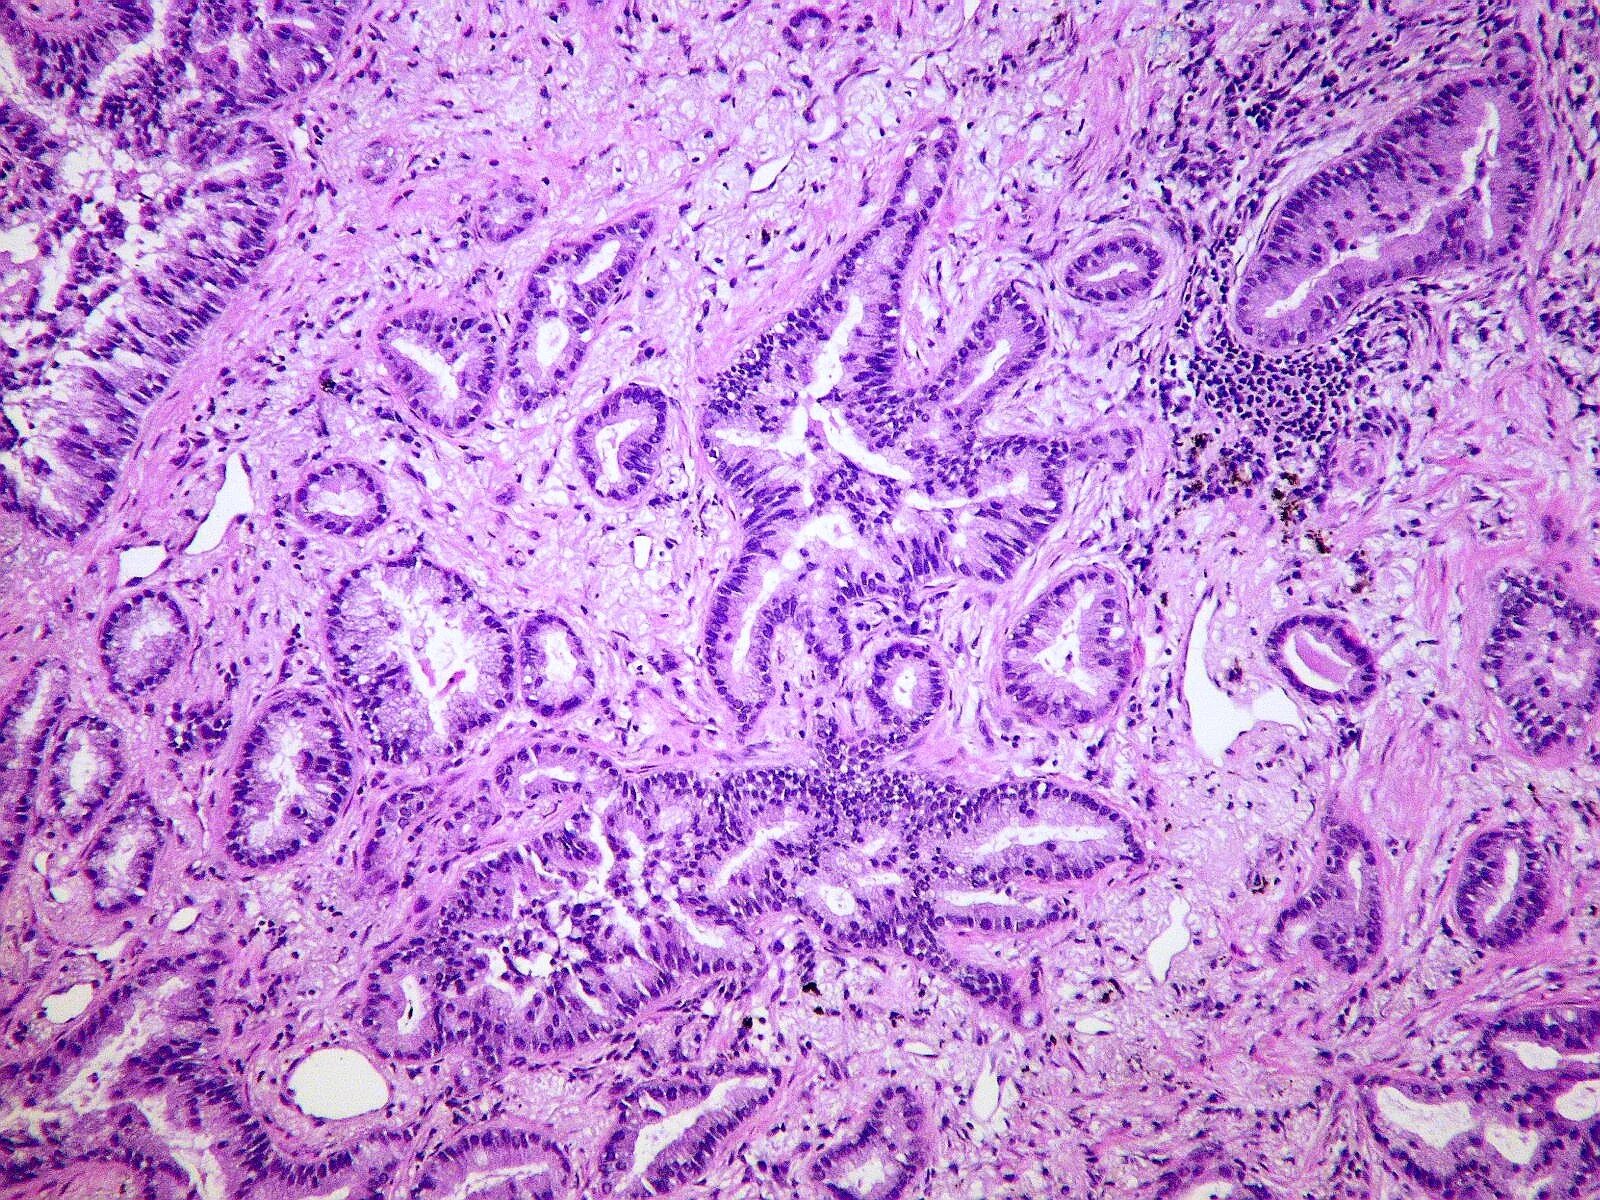

Гистология аденокарциномы